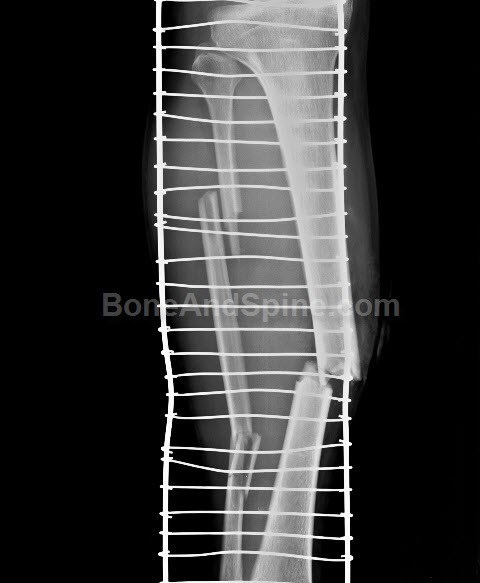

Una fractura es una ruptura o una fisura en un hueso. Una fractura se forma cuando la fuerza que haces contra tu hueso es mayor que la fuerza que puedes soportar normalmente. Por ejemplo en la muñeca, el tobillo, la cadera…

Tipo de Fracturas

-Fractua cerrada

-Fractura Abierta

Fractura de tallo verde

Fractura conminuta

-Fractura de compresión

-Fractura Complicada

Fractura Oblicua

Fractura Espiroidea

Fractura transversal

Fractura Segmentana

Diagnostico

El médico debe realizar una revison física de la lesión y preguntar al paciente sobre los síntomas que presenta. También pueden utilizar las tomografías computarizadas y la resonancia magnética, que ayudan a diagnosticar rápidamente las fracturas.

Algunas fracturas más complicadas pueden necesitar cirugía, tracción quirúrgica o ambas.

Dependiendo de dónde sea la fractura y la gravedad que tenga, el tratamiento puede necesitar:

◦ Buscar apoyo para el hueso.

◦ Un molde de yeso para conseguir apoyo e inmovilizar el hueso, para que no lo pueda mover

◦ Placas de metal para mantener las piezas de hueso juntas.

◦ El alivio del dolor